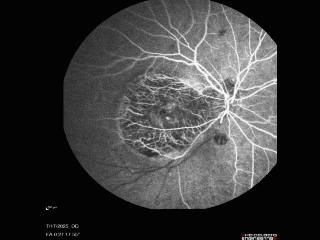

BRAO - plaques in vessels - GIF video of FA

78 year old female with vision loss for 1 week and old macular scar. Images show BRAO with plaques and FA shows occlusion.